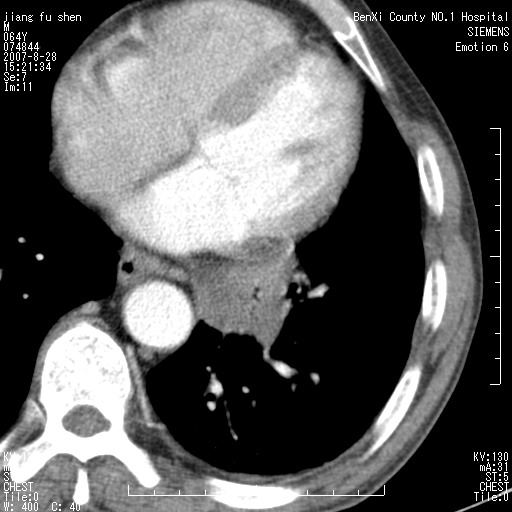

男、64、咳嗽、发烧一周、左肺呼吸音稍弱。既往肺结核,右手结核。

本次扫描患者未带原片,左肺下叶发现病灶。左肺上叶空洞,5组淋巴结肿大,1cm左右。

左肺下叶前内基底段支气管明显偏心性狭窄,周围分叶状肿块,伴有阻塞性肺炎,支持肺癌可能性大。

考虑左肺中央型肺癌并阻塞性肺炎

病灶边缘可见多量较长棘影及纤维条索状影,除外病灶边缘较光整,病灶有分叶表现,但多表现为较浅分叶,且向周围伸出之叶多呈尖角改变,且边缘较光整,病灶增强呈中度延时增强,且早期及中期仅轻度增强,结合患者病史,多考虑继发型肺结核,炎性增殖灶形成,不除外肺癌

左下叶支气管变窄,管腔光滑。软组织形状不规侧,分叶呈角形。结合病史考虑结核可能性大。肺癌不除。